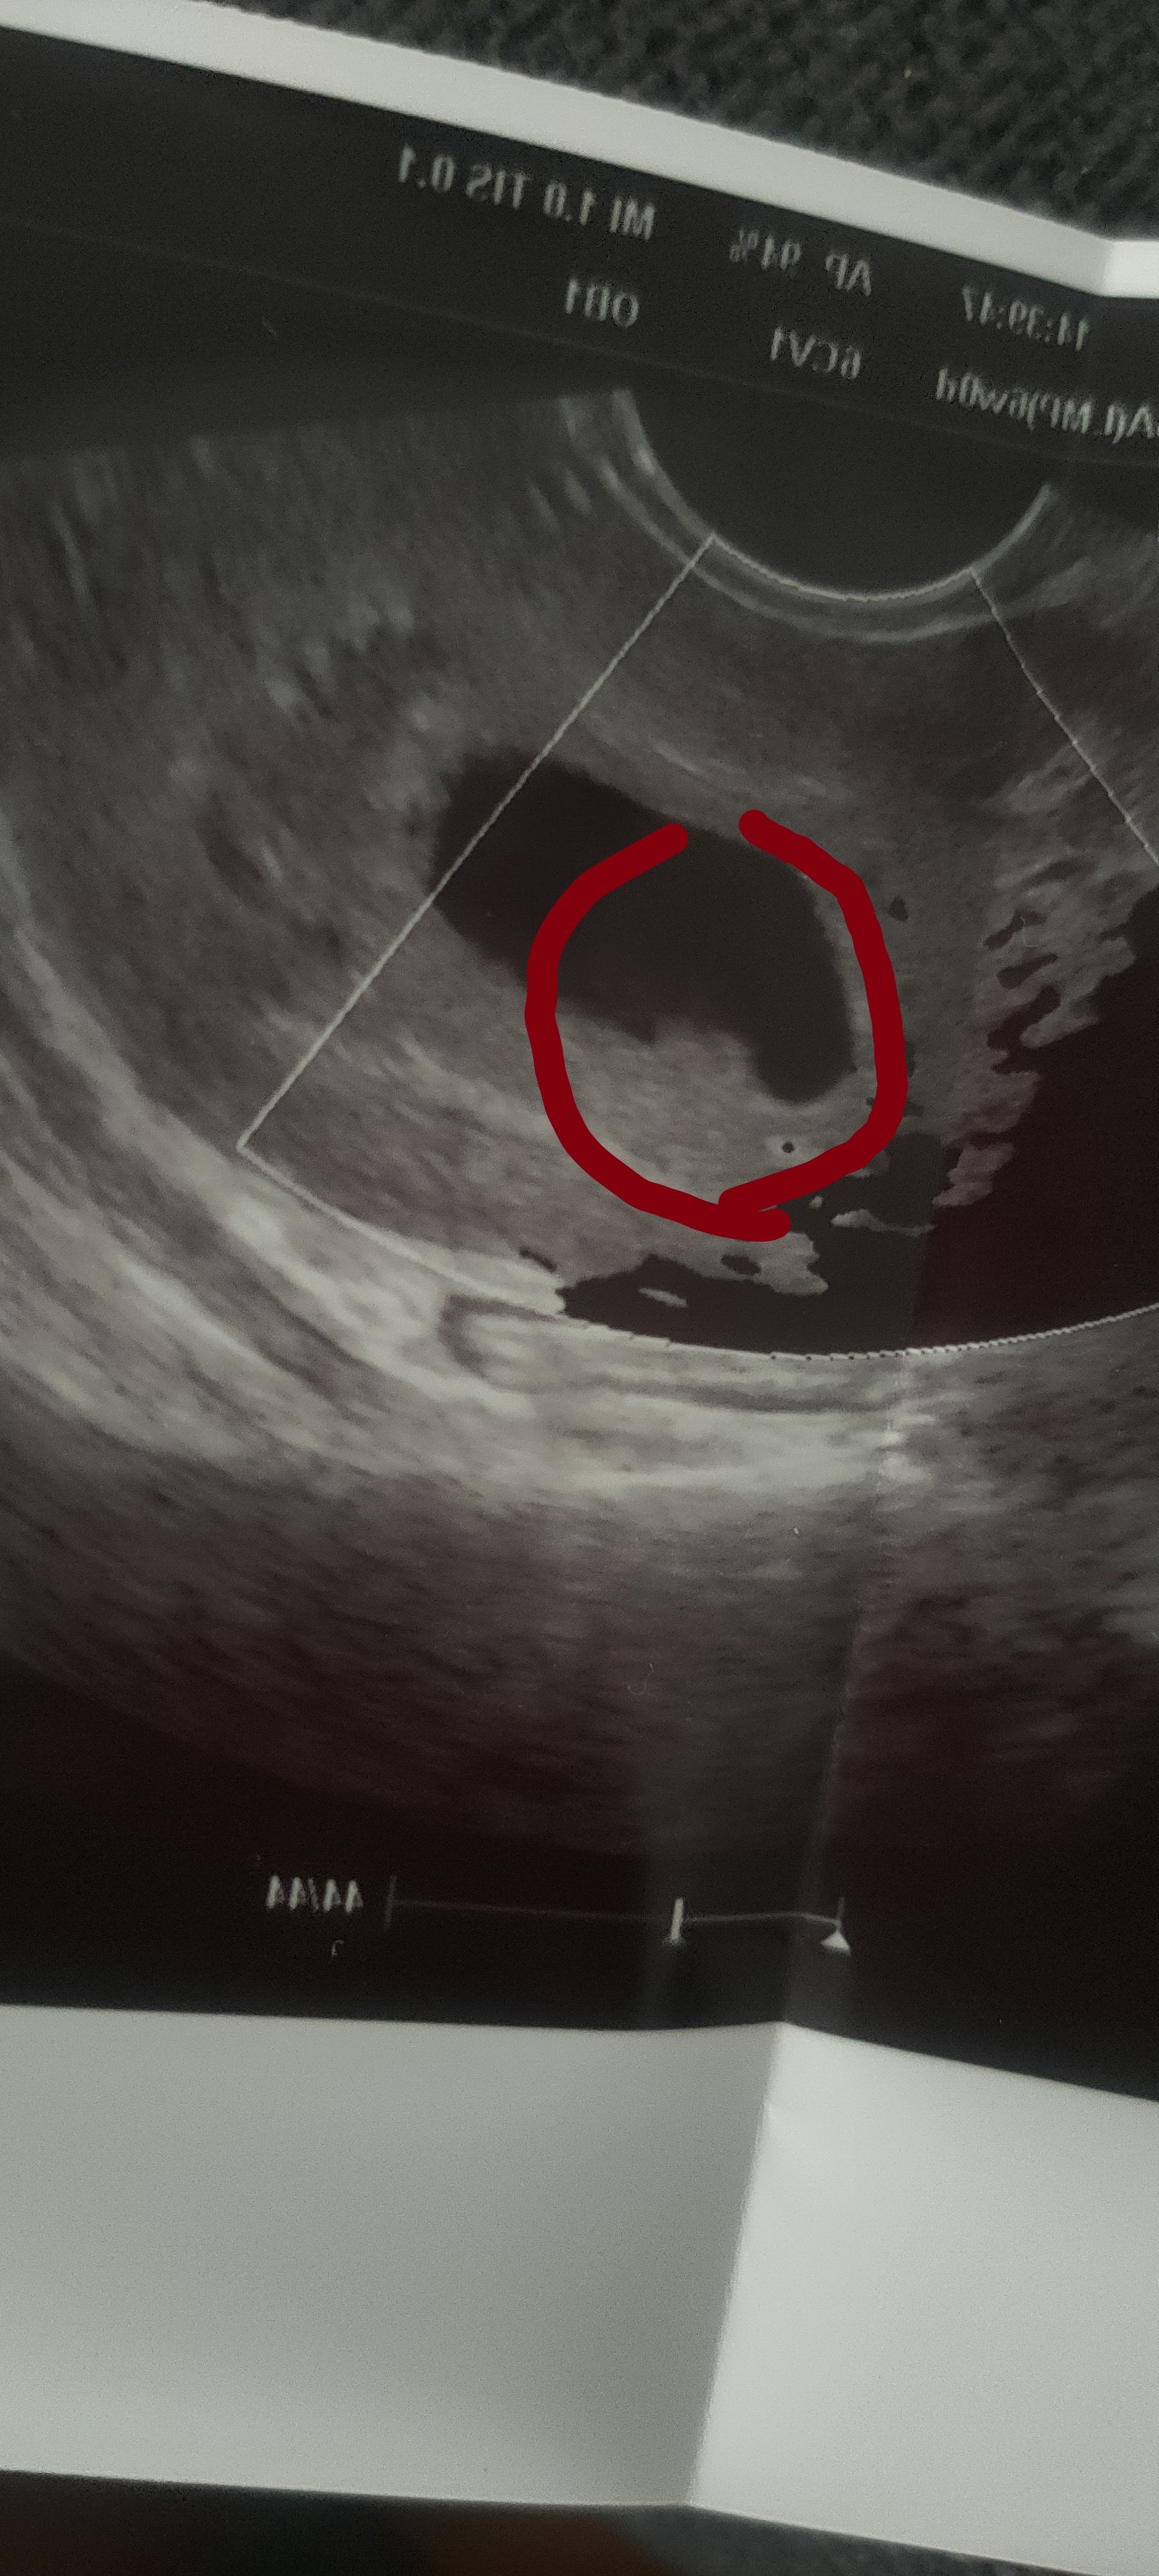

Byłam jeszcze u mojego lekarza prowadzącego. Miałam u niego monitoring więc wiemy że owulacja była wcześniej, dlatego nie wygląda to dobrze

jutro ma dyżur w szpitalu, mam się zgłosić rano na izbę i będę znów lyzeczkowana. Pytałam czy nie możemy spróbować z tabletkami ale powiedział że i on miałby przez to kłopoty i ja, podobno cytotec jest już nielegalny